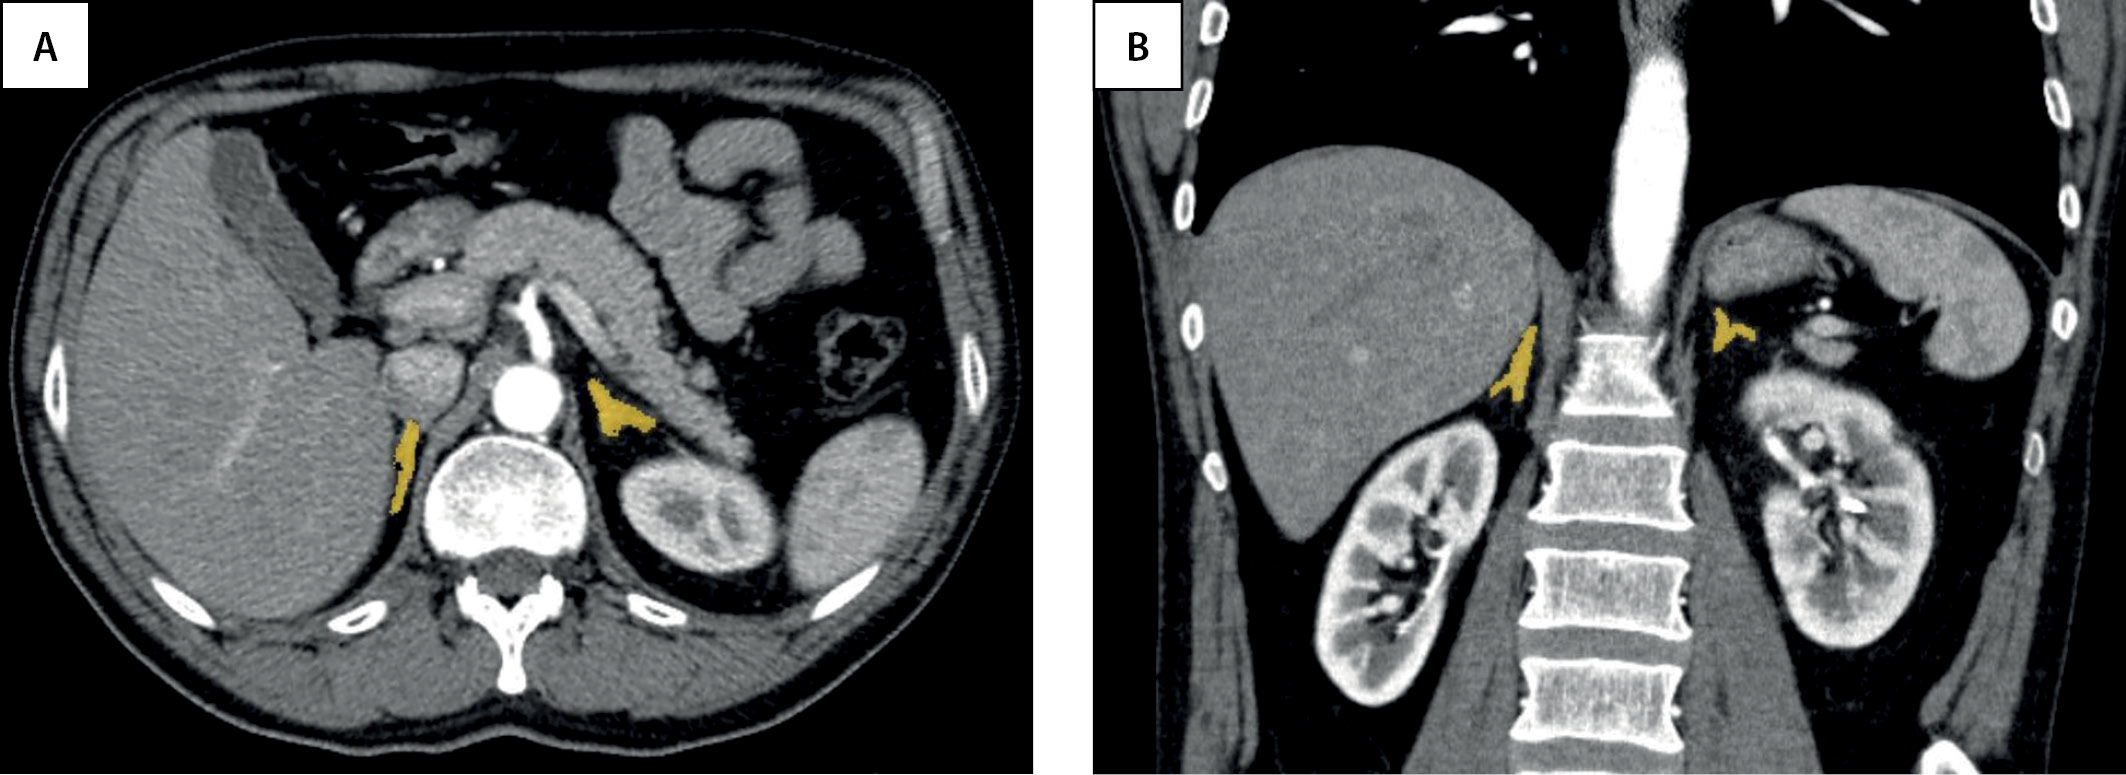

На аксиальных срезах КТ и МРТ каждый надпочечник представляет собой структуру вариабельной формы (линейной, треугольной, Y- или V- образной), длиной до 4,5 см, высотой в среднем до 2 см и толщиной около 1 см [8] (рис. 1). С помощью данных методов надпочечники могут быть визуализированы даже у детей первых лет жизни, так как толщина ножек надпочечников превышает толщину ножек диафрагмы.

Рисунок 1. Нормальные надпочечники на КТ-изображениях с внутривенным контрастным усилением в аксиальной (A) и корональной (B) проекциях.